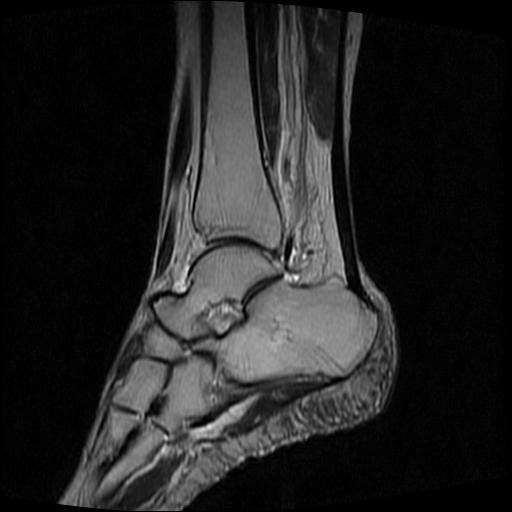

女性,70岁,右侧跟骨疼痛2个月,负重时加剧,不负重时不疼。

胫骨下段,跟骨、距骨可见斑片状异常信号区;考虑:转移瘤

跟骨长t1长t2信号异常,边缘模糊(肿瘤一般边界清楚,故肿瘤不考虑),压脂像呈高信号--骨髓水肿(炎症?)。